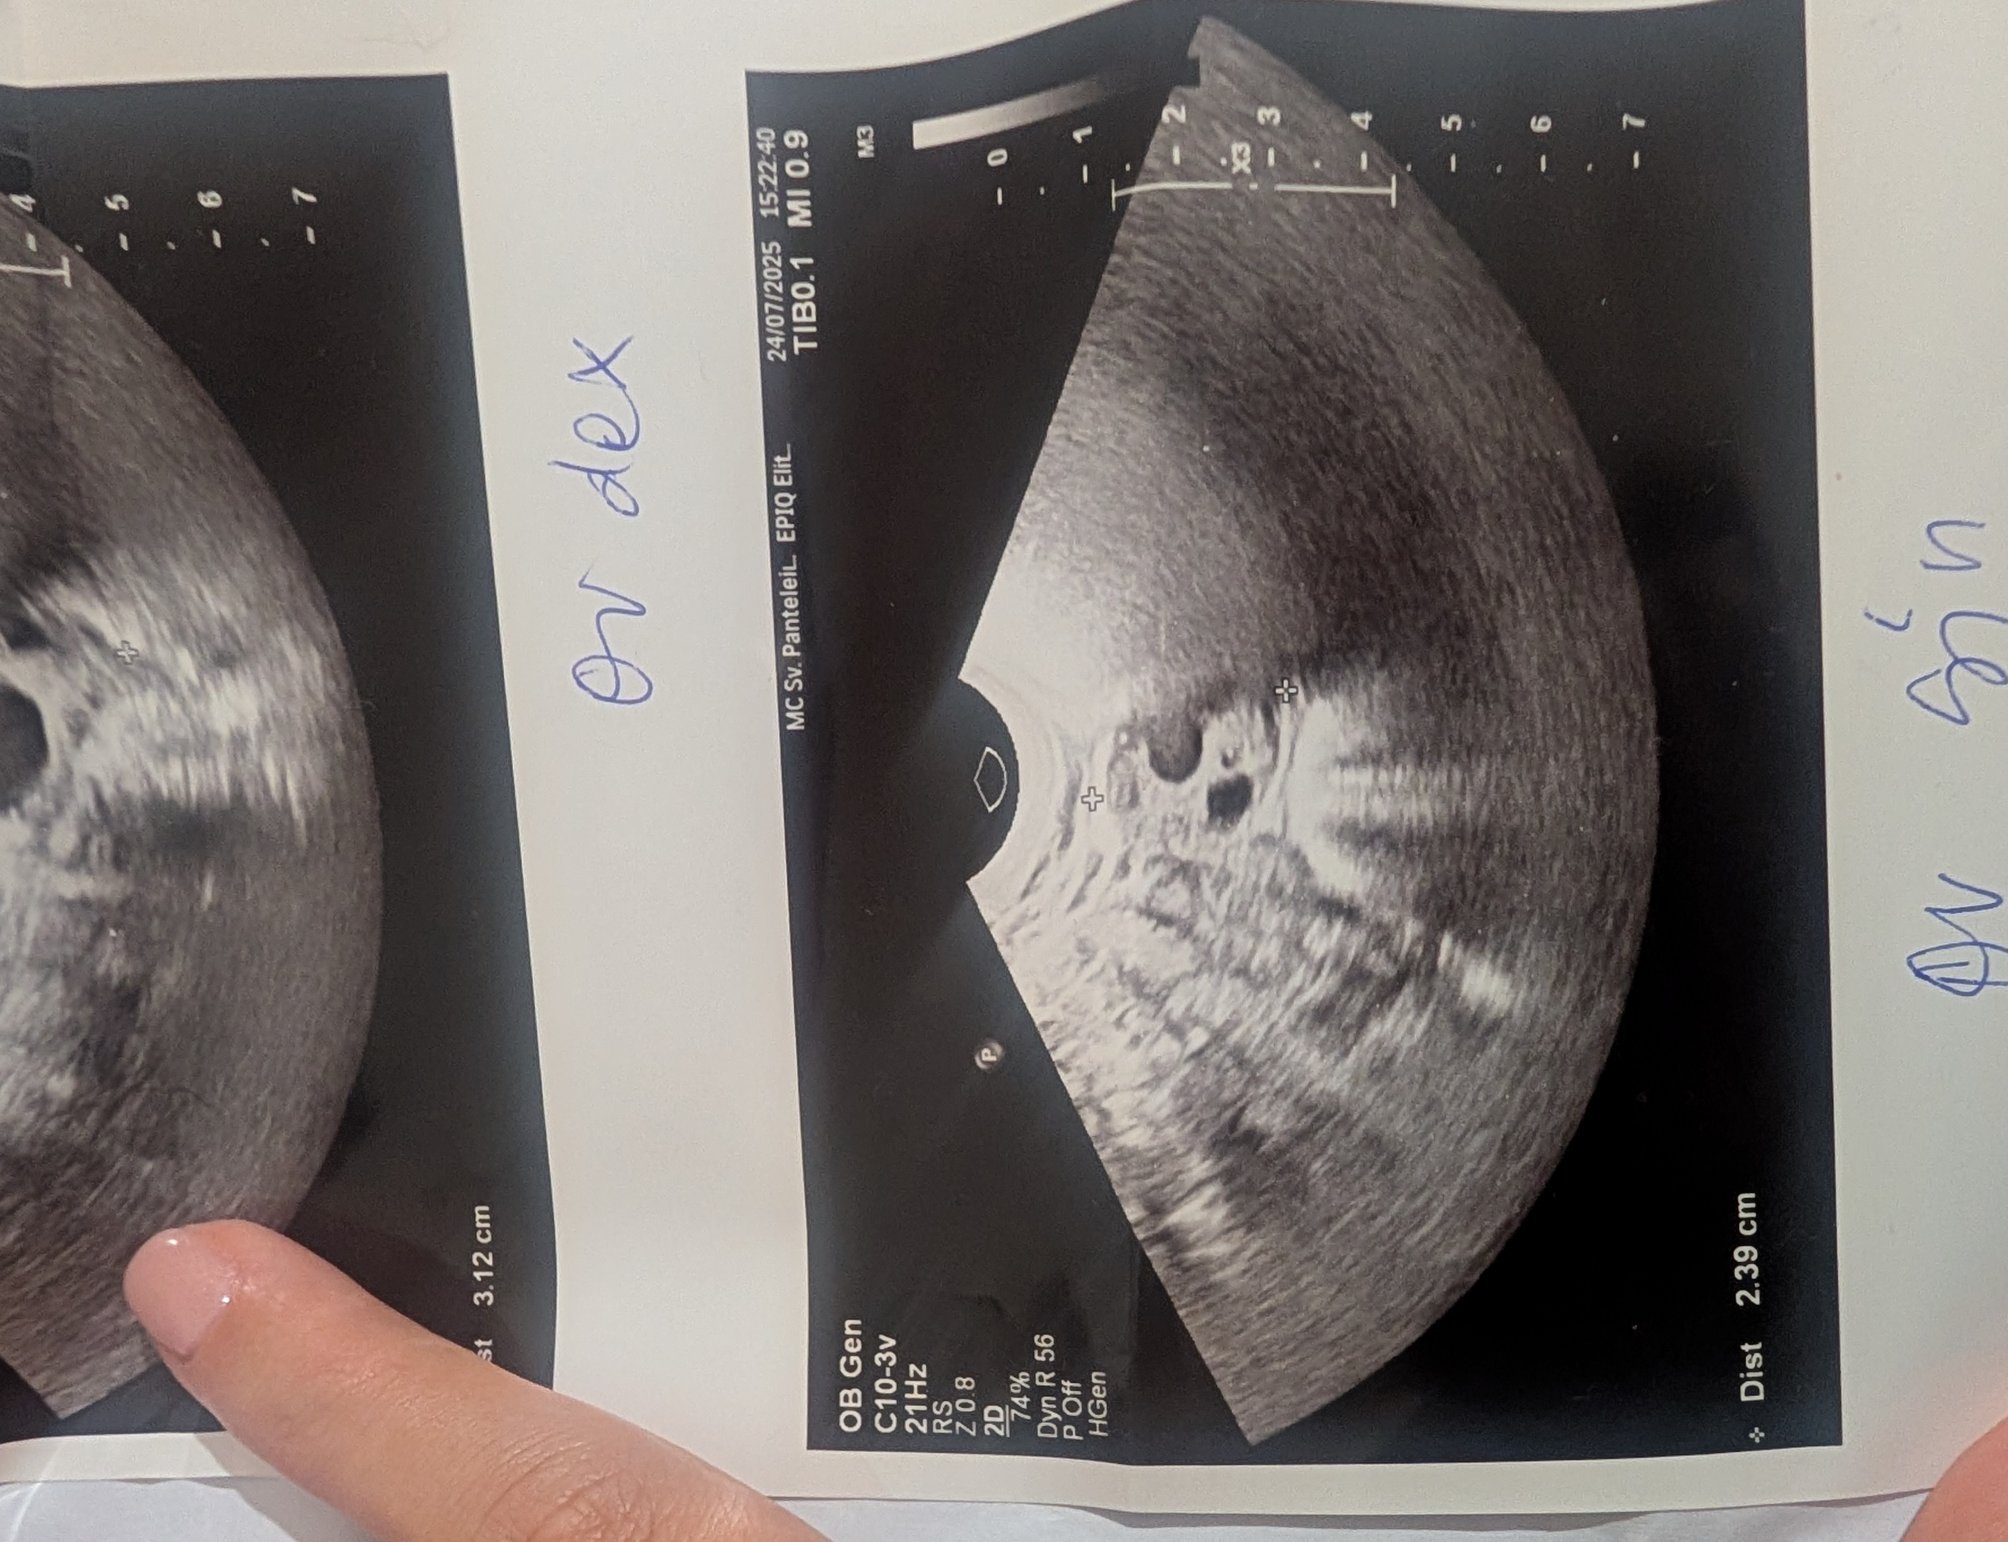

Какво представлява жълтото тяло на ехографската снимка?

-

Какво представляват черните точки в матката на ехографската снимка?